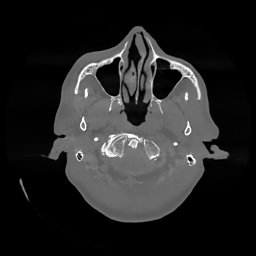

The results for simulated noisy data are shown in Fig. 2. The first and third rows display two representative slices from the test set, and the second and fourth rows present the corresponding error maps. The traditional WCE method suppresses cupping artifacts and recovers some missing anatomical structures but still shows noticeable deviations from the ground truth. Predictions from the four diffusion-based models demonstrate a markedly improved ability to restore anatomical structures. Among them, cDDPM fails to fully reconstruct the patient bed and retains residual noise in its outputs. This noise is attributable to an incomplete reverse denoising process rather than residual Poisson noise, as evidenced in our noise-free experiments (Fig. 5 in the Appendix). PatchDiffusion, diffusionGAN, and I2SB achieve similar visual quality, with I2SB producing the cleanest and most consistent reconstructions.

The experimental results on clinical head data are shown in Fig. 4. The reference images were reconstructed using the fast iterative shrinkage-thresholding algorithm (FISTA) with total variation regularization from non-truncated projection data. In the WCE reconstructions (Fig. 4(b)), severe truncation prevents accurate recovery of anatomical structures outside the FOV. Despite being trained solely on simulated data with a domain gap, all deep learning models can restore a substantial portion of the missing anatomy. Among them, the diffusion-based methods recover soft-tissue boundaries more faithfully than the conventional deep learning approach FBPConvNet, highlighting their stronger image generation capability. However, cDDPM reconstructions exhibit more noticeable noise than those from other methods, consistent with the simulated data results. The patchDiffusion model introduces artifacts within the FOV, likely due to its patch-wise processing strategy. While I2SB shares the same limitations as other diffusion models in perfectly restoring soft-tissue detail, it produces fewer residual noise patterns and fewer artifacts within the FOV boundaries. Overall, Fig. 4 demonstrates the strong efficacy of I2SB in reconstructing real CBCT data.